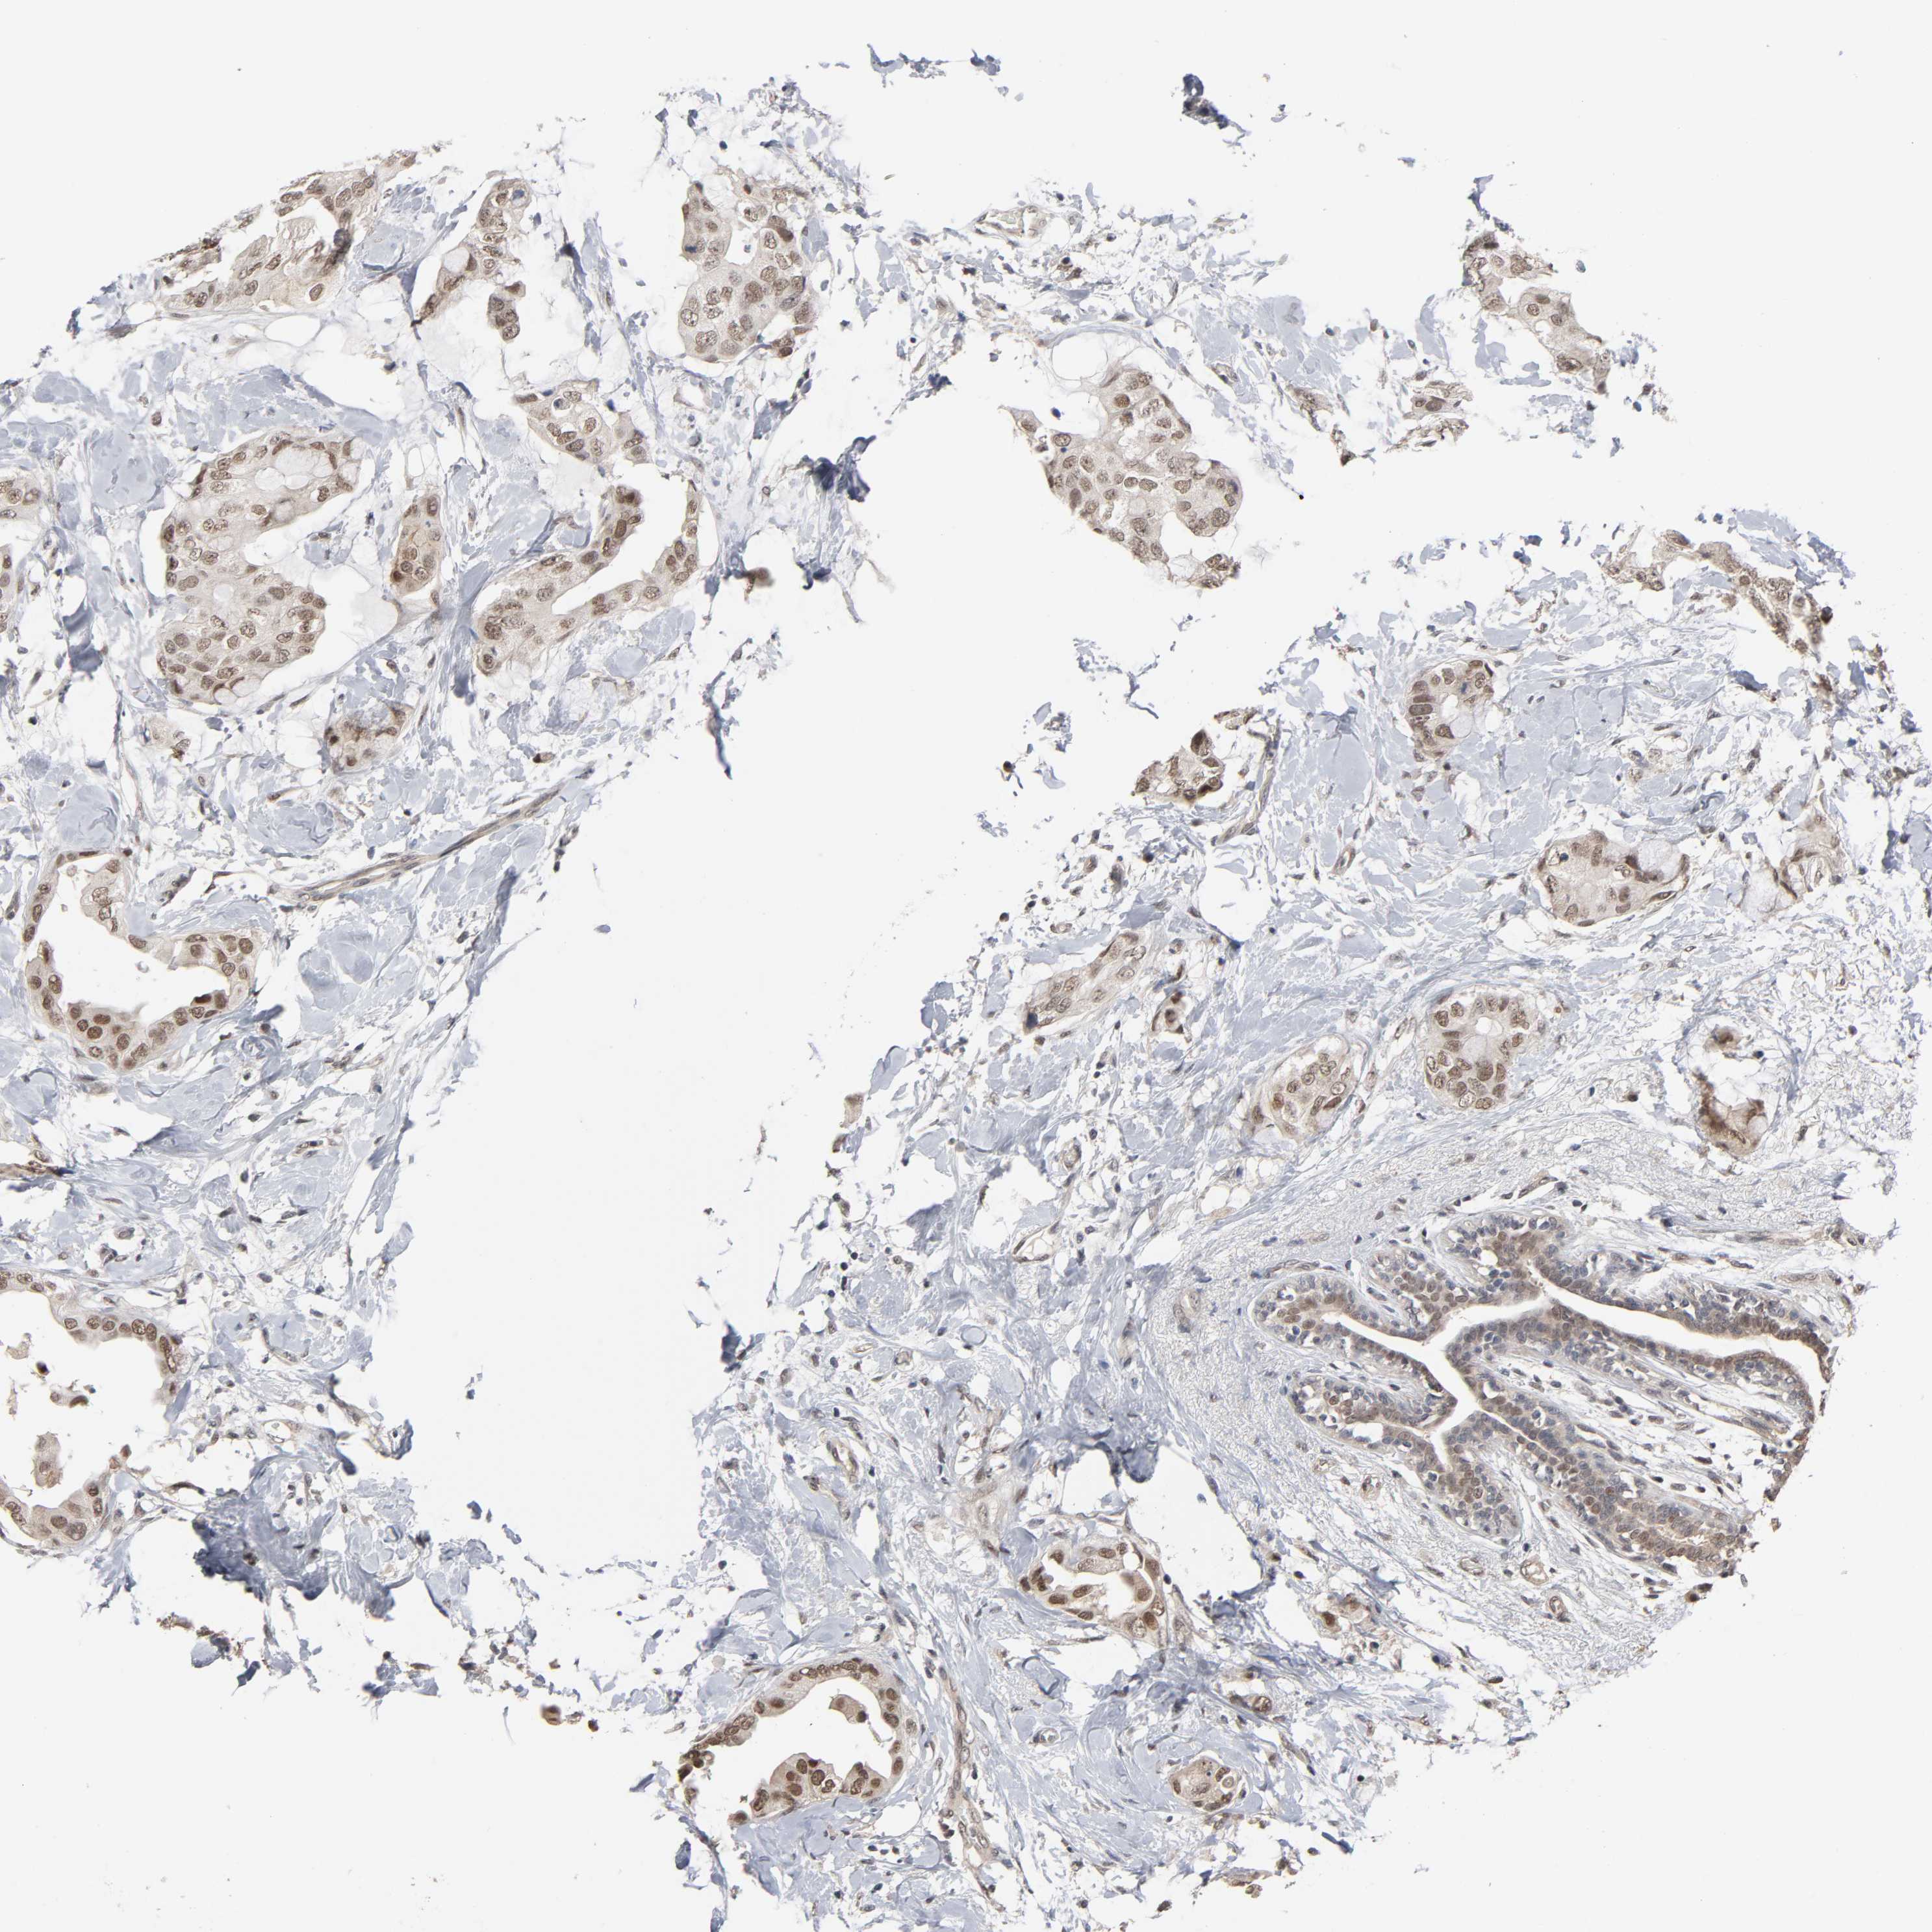

CANCER BREAST CANCER Show tissue menu

BRCA TCGA BRCA VALIDATION PROTEIN EXPRESSION